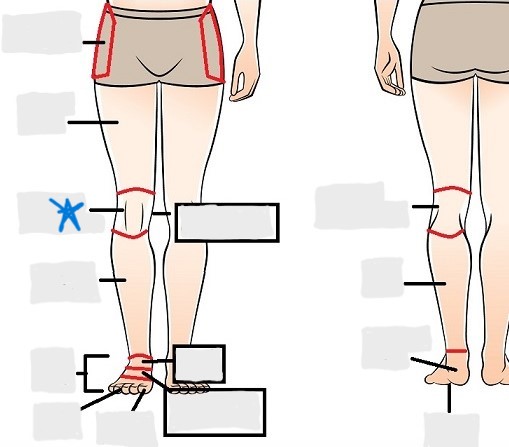

appendicular

coxal

femoral

patellar

popliteal

crural

sural

peroneal

calcaneal

plantar